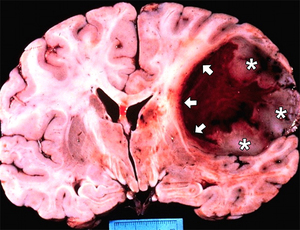

Например, доброкачественные опухоли, расположенные в области мозга, могут приводить к повышению внутричерепного давления и вызывать неврологические симптомы, такие как головные боли, нарушения зрения или координации. В таких случаях, даже если опухоль сама по себе не является злокачественной, ее влияние на здоровье пациента может быть значительным.